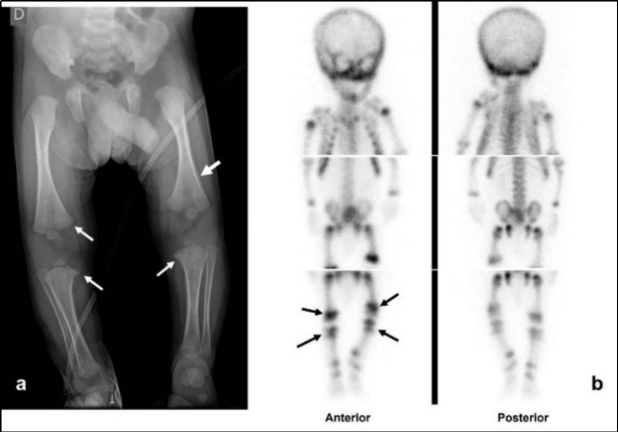

Cuando el estudio radiológico esquelético es normal o ambiguo y existe alta sospecha de maltrato, puede realizarse una gammagrafía ósea (como lo afirma el panel de expertos de American College of Radiology, ACR: “Indicado cuando la sospecha clínica de abuso sigue siendo alta y todavía es necesaria la documentación” )(15).

El centellograma óseo también puede realizarse como una alternativa a la seriada esquelética en niños entre 2 y 5 años, ya que la probabilidad de lesión metafisaria clásica es baja en este grupo de edad (Fig. 5). Conway et al. y otros, en un informe de dos estudios y una revisión de la literatura, concluyen que la gammagrafía esquelética es el mejor estudio complementario para la evaluación de la sospecha de abuso infantil(13). La gammagrafía puede identificar fracturas agudas de costillas que no son evidentes en las radiografías, pero es menos sensible en la detección de las fracturas metafisarias (Fig. 6) y fracturas de cráneo (13,16).

Habitualmente en nuestras instituciones el centellograma esquelético se realiza sin anestesia; se intenta privar antes al niño de sueño, indicándole a la persona cuidadora que lo haga conciliar el sueño inmediatamente antes de adquirir las imágenes. El estudio es de gran utilidad ya que los cambios metabólicos preceden a los anatómicos, visualizándose las fracturas aun cuando estas no presenten signos de reparación radiográfica, así como también la distribución y extensión de las lesiones. En nuestro caso fue útil al permitir identificar el compromiso mandibular no detectado en el examen físico ni radiológico inicial.